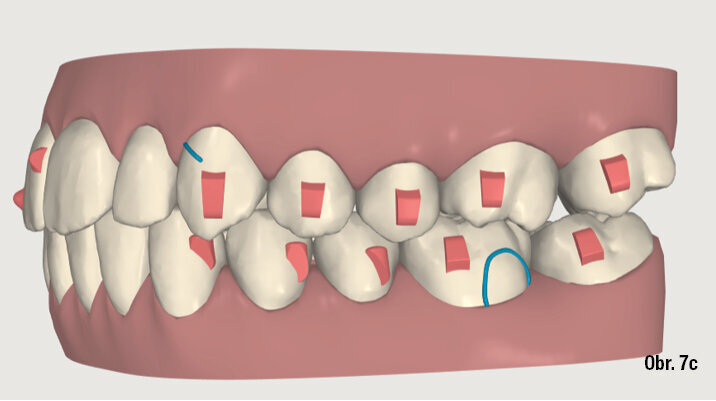

Na překrytí kefalometrických snímků je zřejmá distalizace molárů o 6 mm bez výraznějšího sklonu a s ideálním bukolingválním sklonem řezáků. Tahy druhé třídy umožnily protrakci mandibuly o 1,5 mm. Jako retenční aparáty jsme zvolili Vivera retainery (Align Technology) (obr. 6, 7a–c, 8a–c).